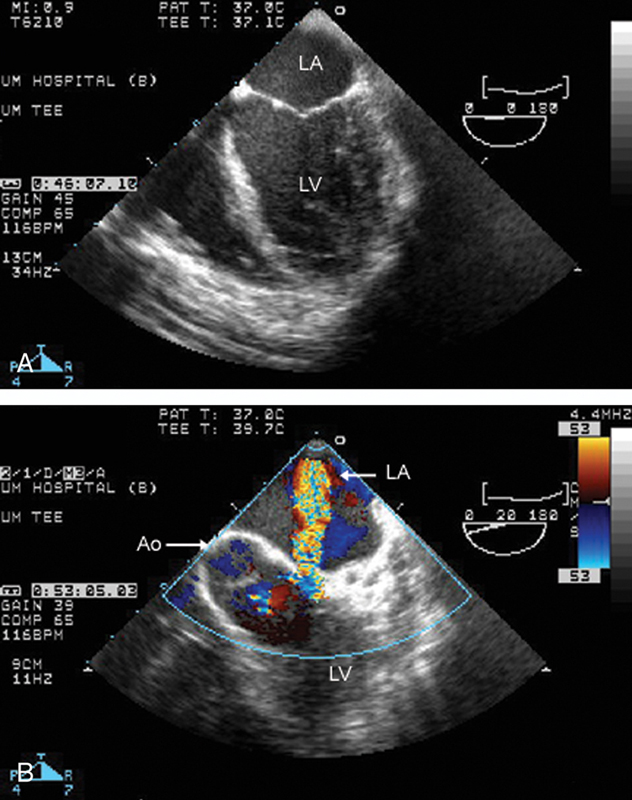

فحوصات تشخيصية لبعض امراض القلب والشرايين التاجية